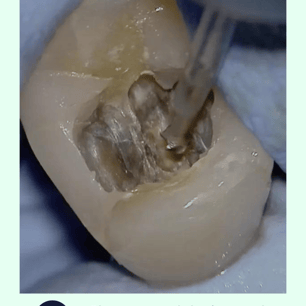

Localización y Remoción de

Calcificaciones: Se utilizan instrumentos especiales, como limas ultrasonicas, para localizar y remover las calcificaciones.